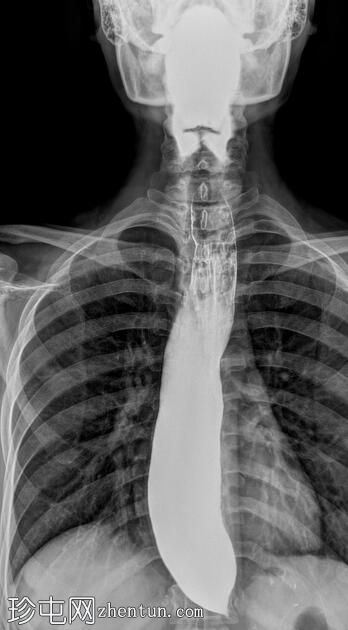

透视检查

正位

食管扩张,远端平滑狭窄并呈锥形(鸟嘴状),符合贲门失弛症的特征性表现

食管黏膜形态正常,无异常或溃疡

未见食管裂孔疝

钡餐检查显示食管扩张,远端狭窄并呈锥形,形成符合贲门失弛症特征的鸟嘴状外观。